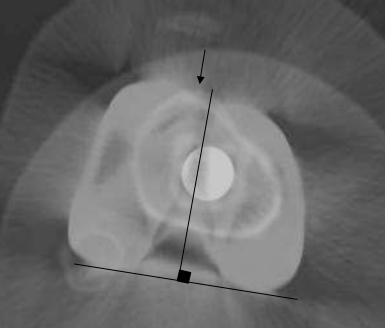

Evaluation de la rotation prothétique

- Ligne bicondylienne – Embase Tibiale

- Poly Ethylène – Embase Tibiale

Rotation Globale: TAGT